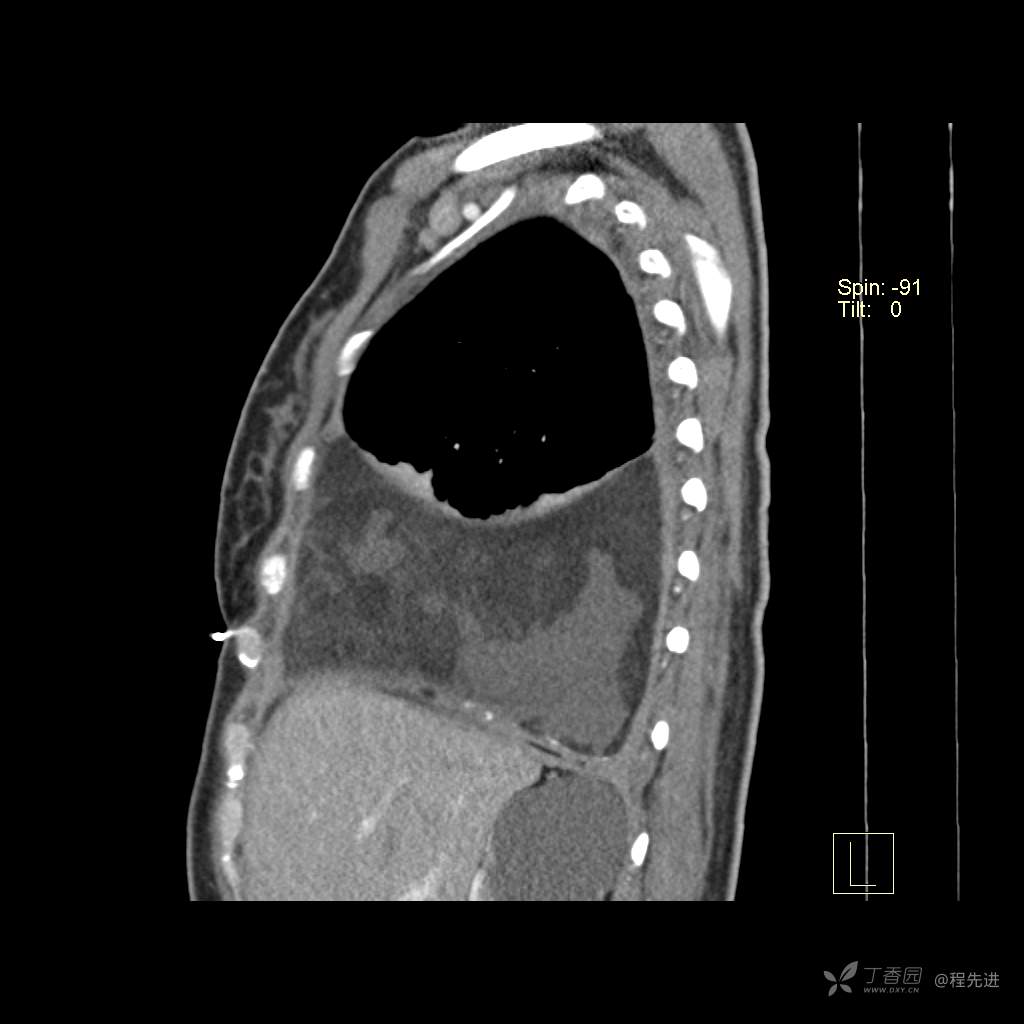

患者性别:女

患者年龄:51岁

简要病史:胸闷半年